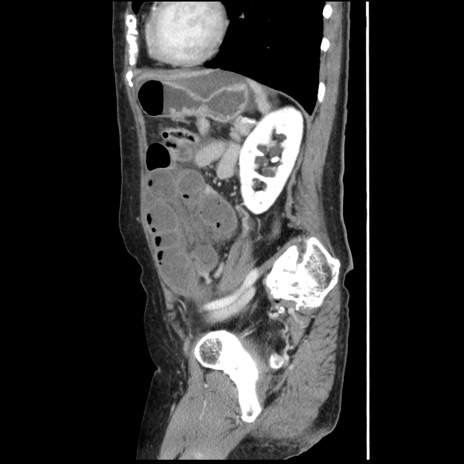

冠状断像

【症例】80歳代女性

【主訴】腹痛

【現病歴】8時間前から腹痛あり来院。

【既往歴】糖尿病、脂質異常症、子宮体癌にて子宮全摘術

【身体所見】意識清明・会話良好だが腹痛で苦悶様、全腹部にわたって反跳痛と圧痛あり

【データ】WBC 13600、CRP 0.14、LDH 224、CK 90